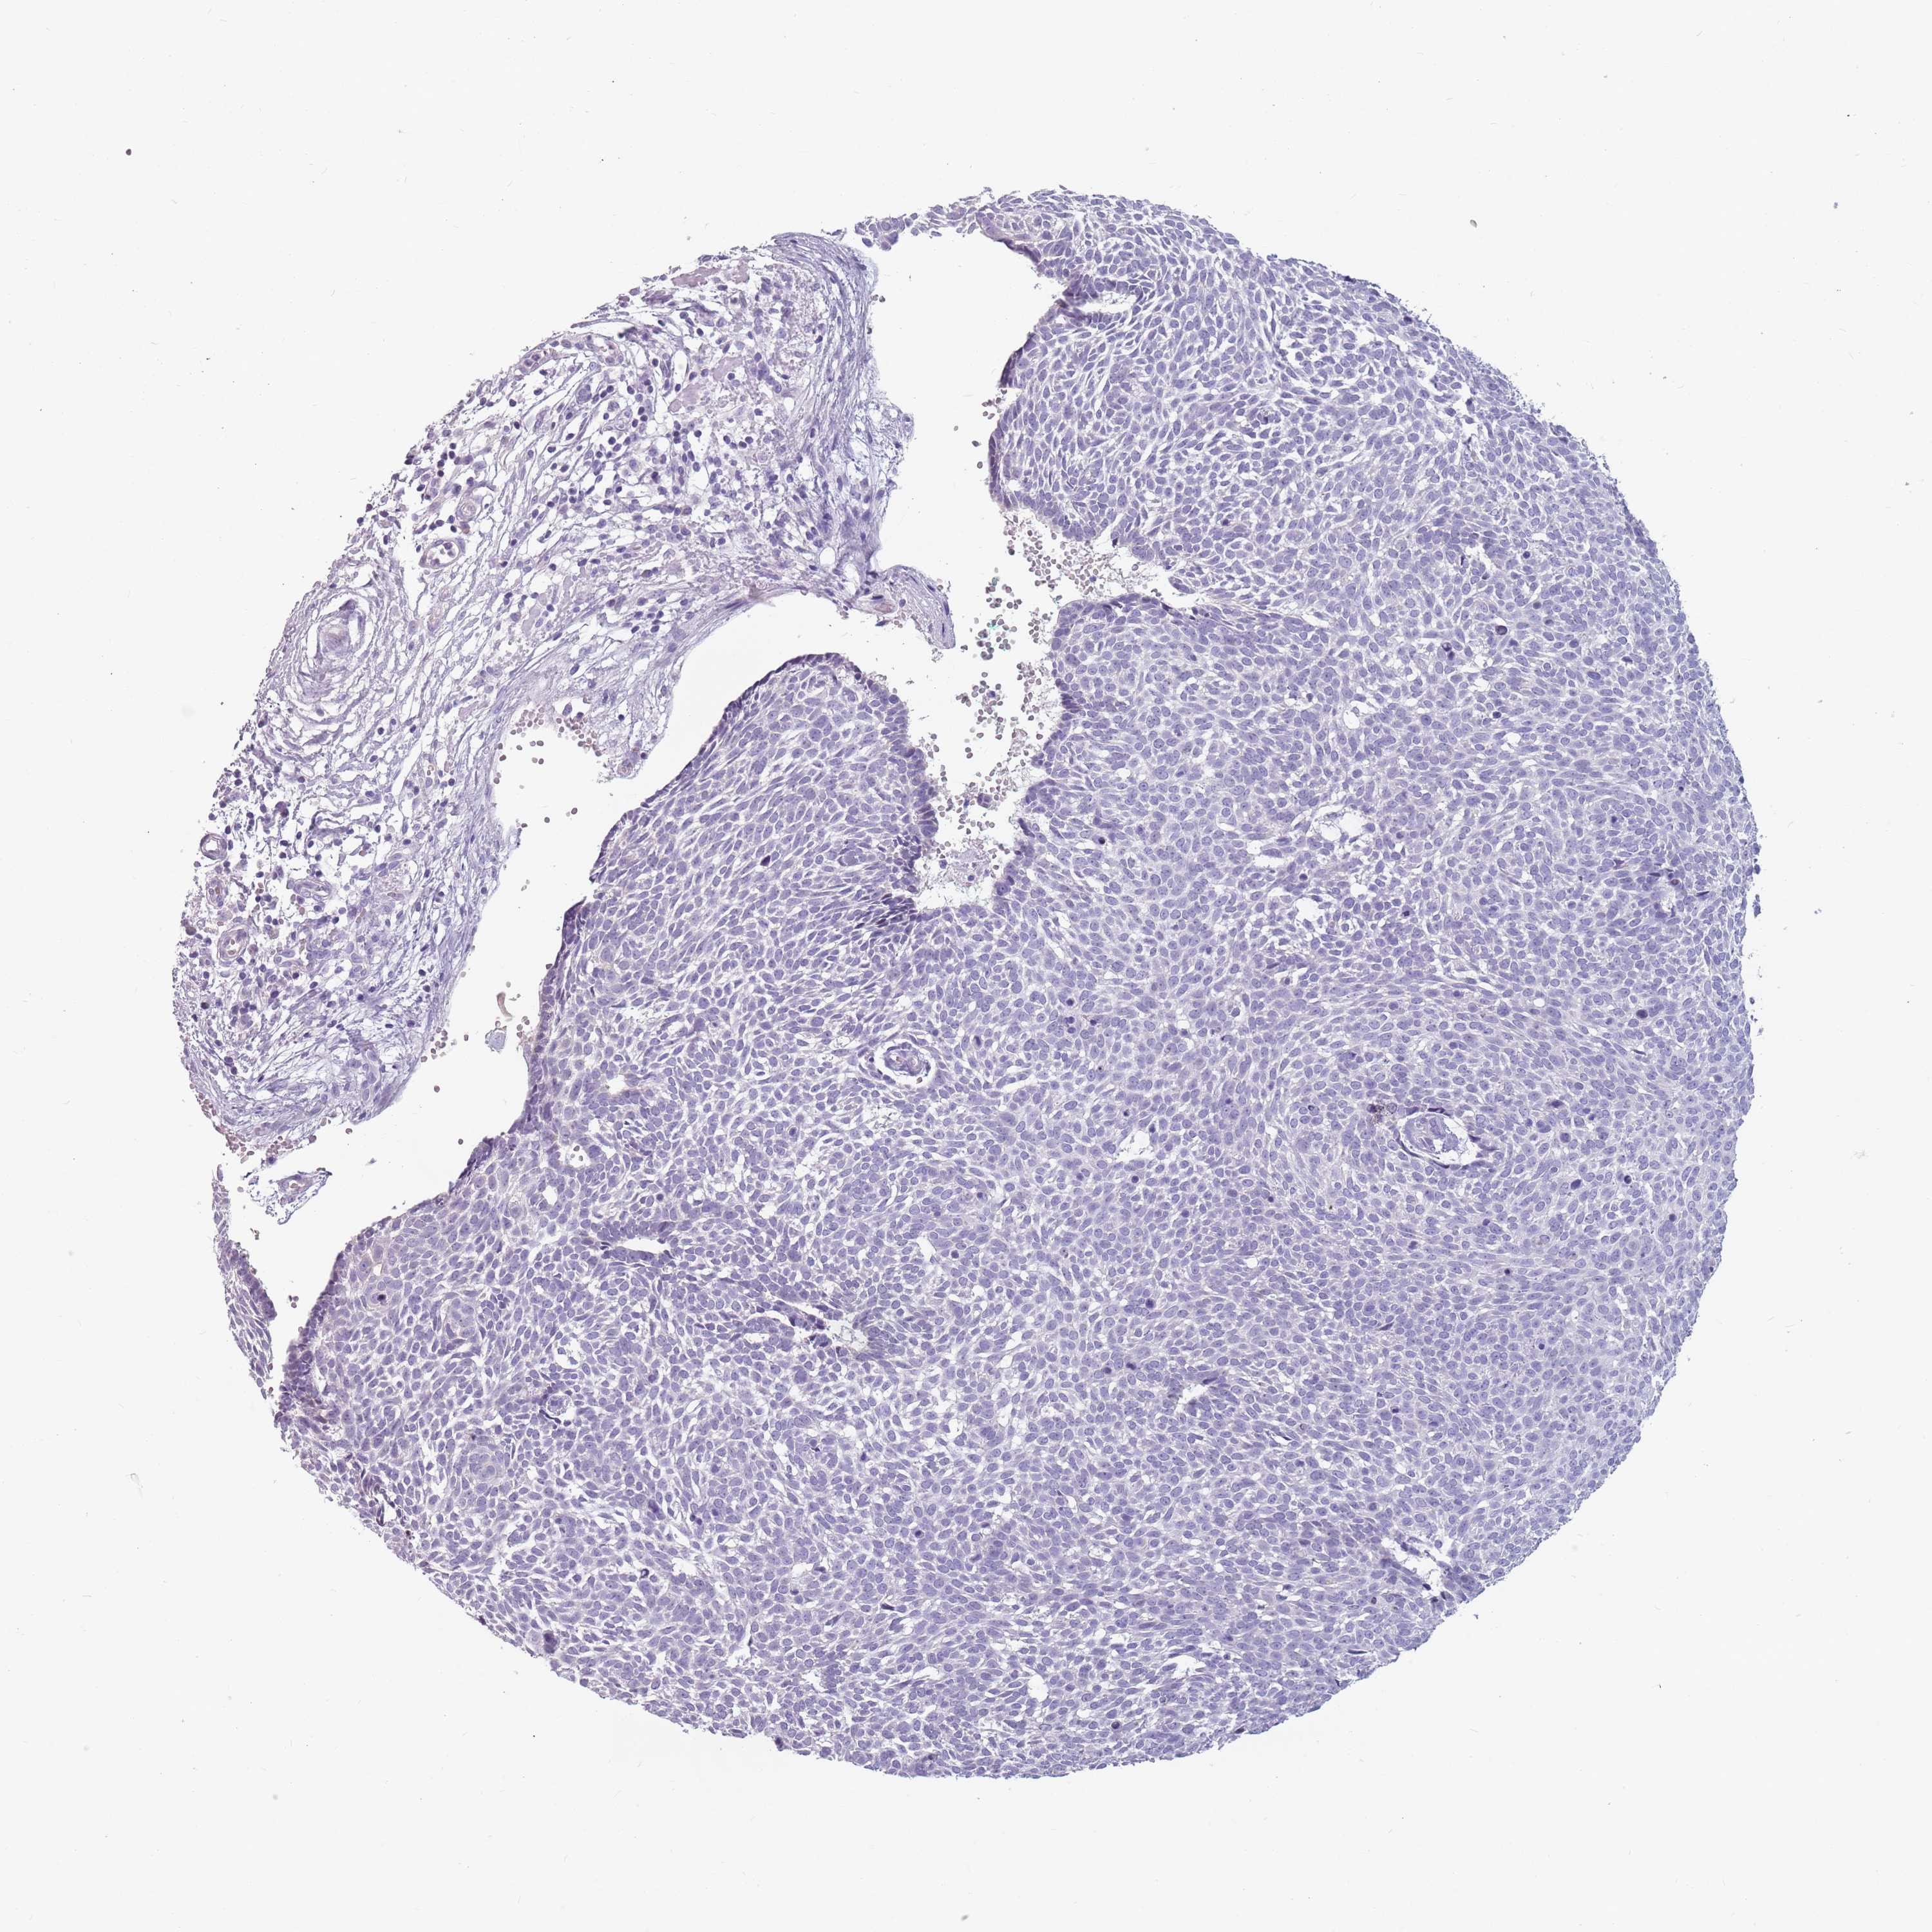

Basal cell and squamous cell cancer

SKIN CANCER - Protein expressioni

A mouse-over function shows sample information and annotation data. Click on an image to view it in a full screen mode. Samples can be filtered based on level of antibody staining by selecting one or several of the following categories: high, medium, low and not detected. The assay and annotation is described here.

Antibody stainingi

Antibody staining in the annotated cell types in the current human tissue is reported as not detected, low, medium, or high, based on conventional immunohistochemistry profiling in selected tissues. This score is based on the combination of the staining intensity and fraction of stained cells.

Each image is clickable and will lead to virtual microscopy that enables deeper exploration of all samples and also displays staining intensity scores, fraction scores and subcellular localization as well as patient and tissue information for each sample.

Antibody HPA047614

Staining

High

Medium

Low

Not detected

Intensity

Strong

Moderate

Weak

Negative

Quantity

>75%

75%-25%

<25%

None

Location

Nuclear

Cytoplasmic/membranous

Cytoplasmic/membranous,nuclear

Basal cell carcinoma

Squamous cell carcinoma, NOS

Squamous cell carcinoma, metastatic, NOS